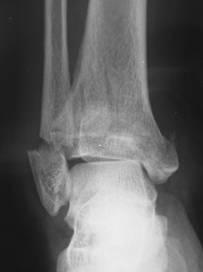

診斷檢查

傳統的軟組織損傷檢查2.注意有無休克或身體其他部位的損傷,有無擠壓綜合徵(以肢體或軀幹腫脹、肌紅蛋白尿及高血鉀等為特點的急性腎功能衰竭)。

3.詳查受傷部位,注意創口的大小、形狀、出血情況、受傷程度及範圍,皮膚有無瘀斑、水皰,皮溫有無改變,指(趾)端循環情況,肌肉有無缺血性壞死,傷肢是否腫脹、皮膚緊張和發硬、能否活動,有無感覺障礙。

4.嚴重創傷(包括擠壓傷)或全身症狀嚴重者,應每日查血、尿常規,記錄尿量,必要時作血、尿生化檢驗(包括肌紅蛋白)、心電圖及腎功能等。